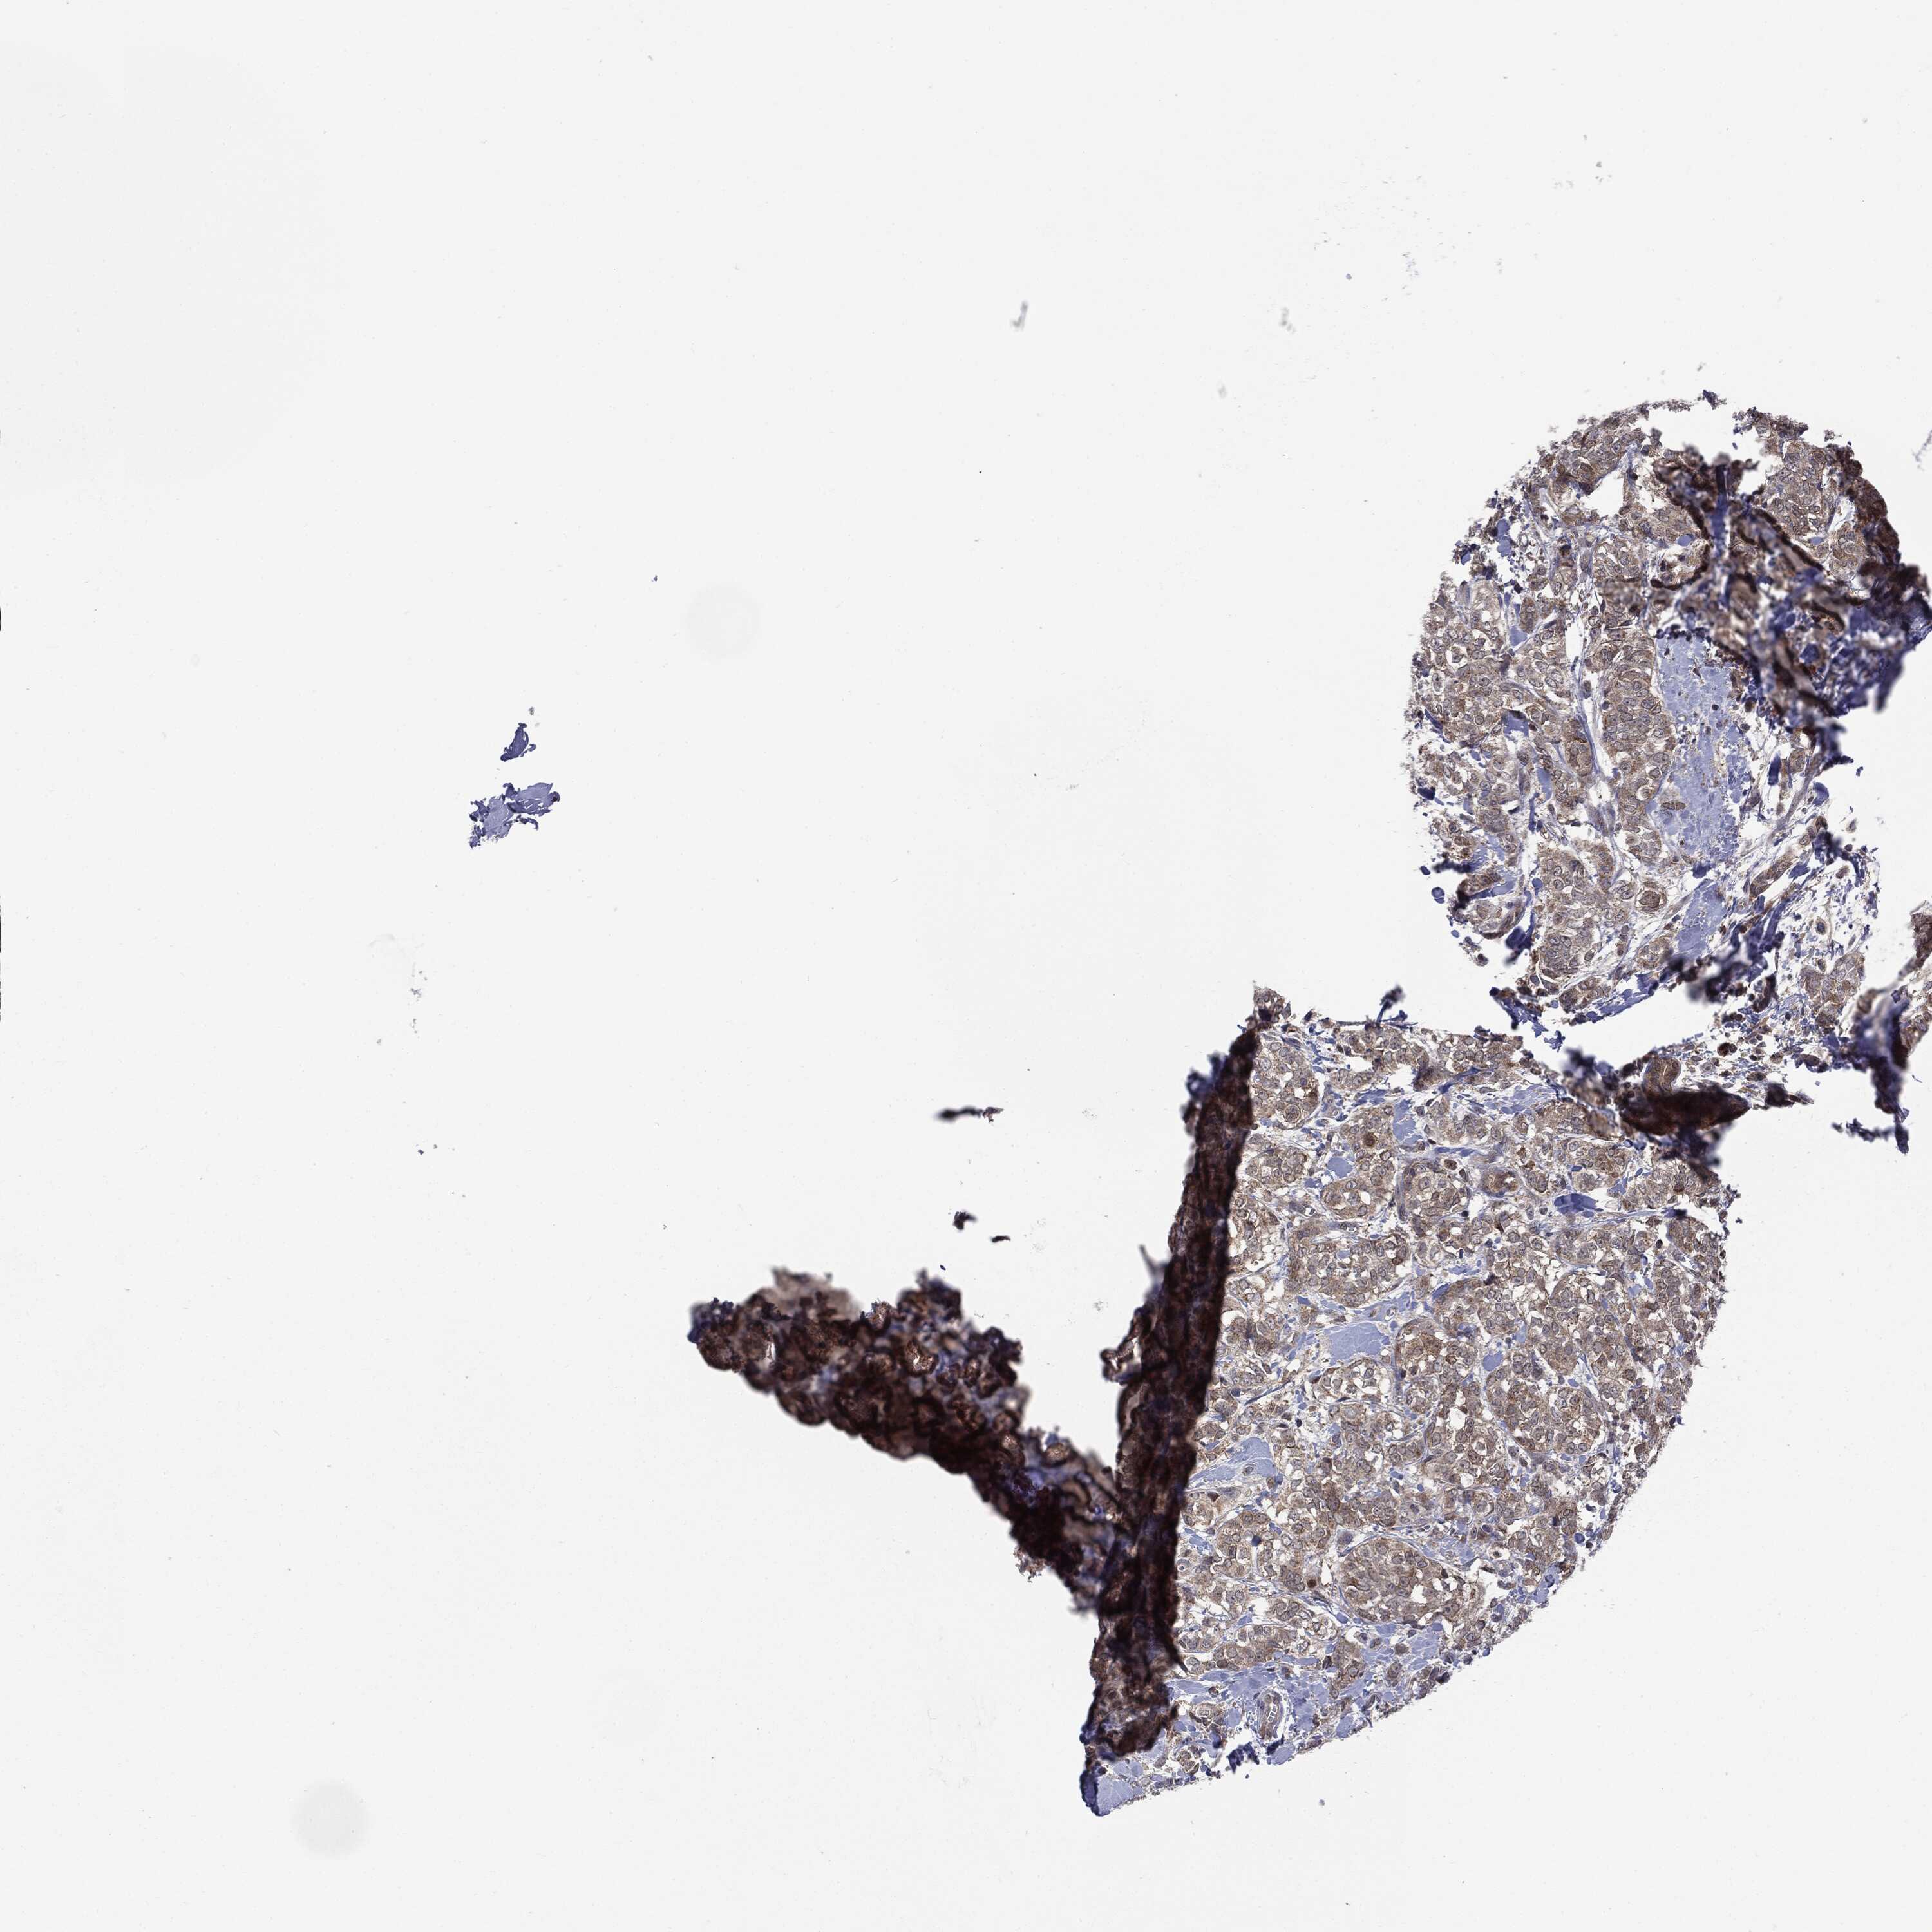

CANCER BREAST CANCER Show tissue menu

BRCA TCGA BRCA VALIDATION PROTEIN EXPRESSION

ANTIBODIES

AND

VALIDATION